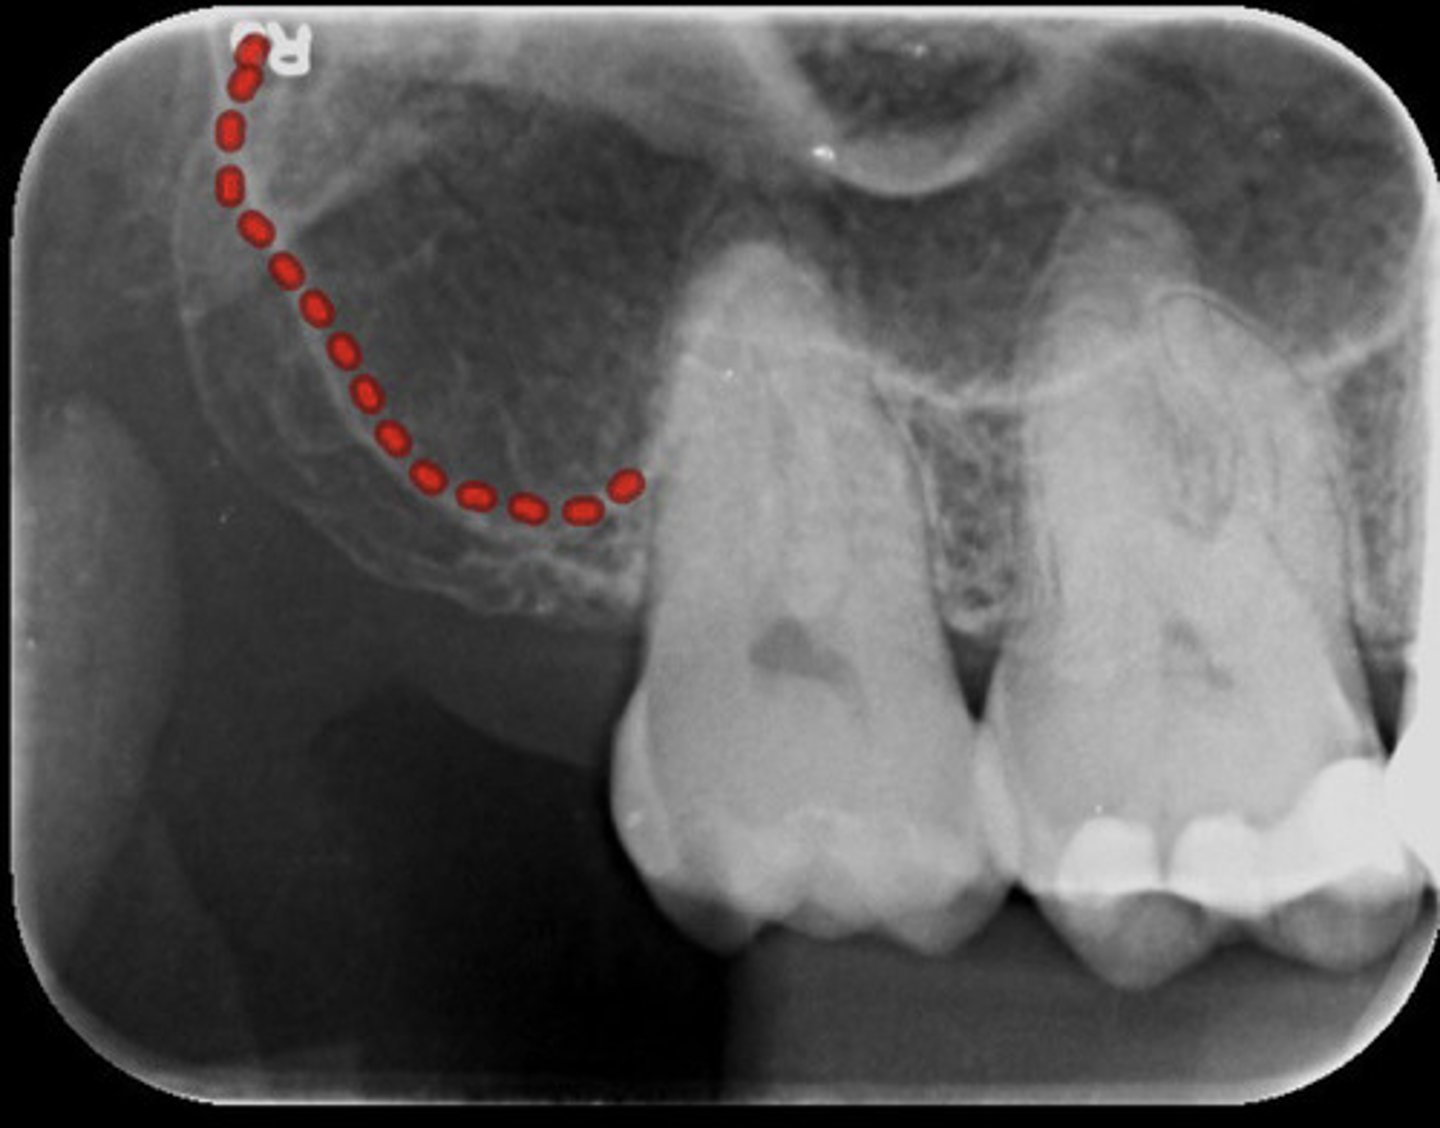

What is the red dotted line circling?

Maxillary sinus